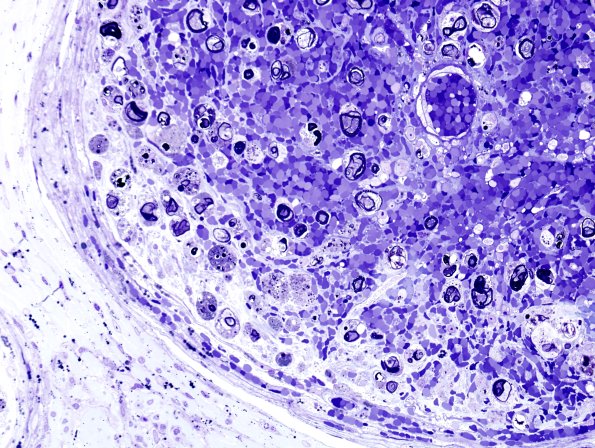

This is not the typical appearance of a PAN fascicle in which there is frank intrafascicular hemorrhage and ongoing axonal degeneration. (plastic section)